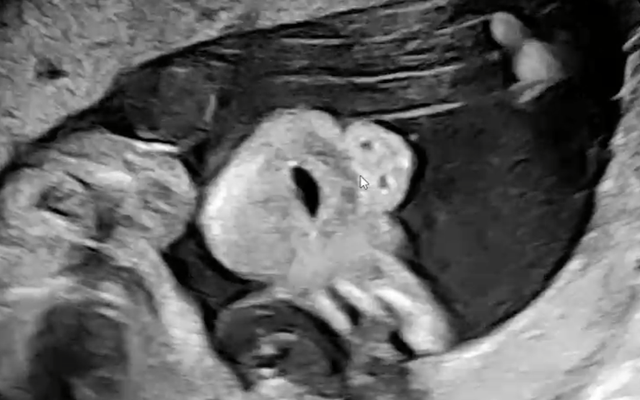

초음파 검사 후 24주인걸 확인하고 흠뻑 혼났습니다 너무 늦게 왔다고....

아들놈인데 얼굴은 다행히도 와이프 닮은거 같고

입벌리고 쳐자는건(?) 저를 닮았네요..